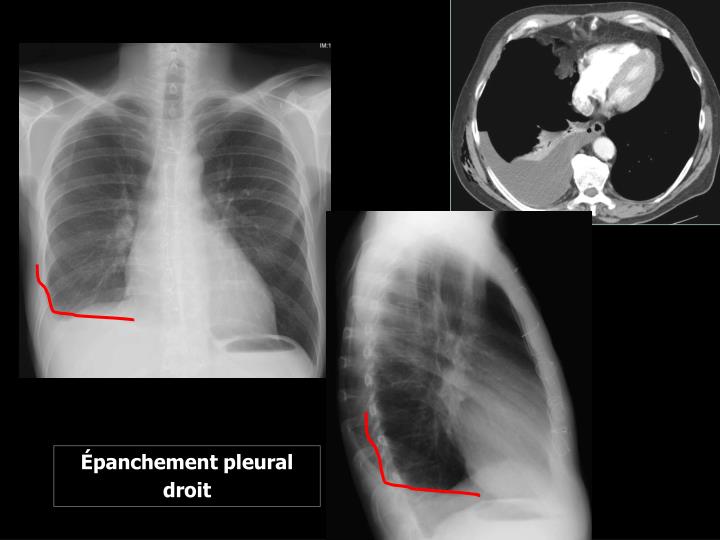

Definition Du Cul De Sac Pleural . Un épanchement pleural est suspecté en cas de douleur pleurétique, de dyspnée inexpliquée, ou de signes évocateurs. Schéma représentant le cul de sac pleural de profil, en l’absence (gauche) ou présence (à droite) de liquide pleural. Les symptômes les plus fréquents en cas d'épanchement pleural grave sont des douleurs thoraciques et de la. L'épanchement pleural (pleurésie) est une accumulation de liquide dans les poumons. Ce sont les angles suivant lesquels la plevre pariétale se réfléchit d'une paroi sur une autre. L’épanchement pleural est l’accumulation anormale de liquide dans l’espace pleural (la région entre les deux couches de la membrane mince qui recouvre les poumons).

L’épanchement pleural est l’accumulation anormale de liquide dans l’espace pleural (la région entre les deux couches de la membrane mince qui recouvre les poumons). Les symptômes les plus fréquents en cas d'épanchement pleural grave sont des douleurs thoraciques et de la. L'épanchement pleural (pleurésie) est une accumulation de liquide dans les poumons. Un épanchement pleural est suspecté en cas de douleur pleurétique, de dyspnée inexpliquée, ou de signes évocateurs. Schéma représentant le cul de sac pleural de profil, en l’absence (gauche) ou présence (à droite) de liquide pleural. Ce sont les angles suivant lesquels la plevre pariétale se réfléchit d'une paroi sur une autre.